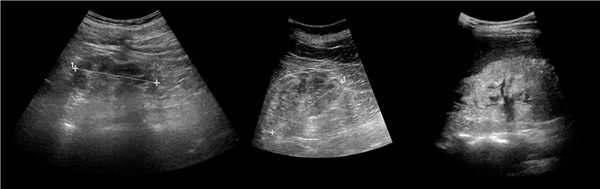

Рисунок. На УЗИ (1) и КТ (2, 3) контур почек волнистый. У эмбриона почка развивается из отдельных долек, которые сливаются по мере их роста. Дольчатое строение почек хорошо видно у плода и новорожденных, в единичных случаях сохраняется у взрослых.

Рисунок. Можно встретить горбатую левую почку — выпуклый неровный наружный контур из-за гипертрофии паренхимы в средней трети почки. Считают, что «горб» формируется у плода под давлением нижнего края селезенки.

Рисунок. Сканирование со стороны передней брюшной стенки позволяет не пропустить перешеек между почками. Перешеек спереди от позвоночника является доказательством сращения почек — подковообразная почка. Варианты анатомии подковообразных почек смотри здесь.

Рисунок. На УЗИ округлое образование разделяет почечный синус на два сегмента с общей лоханкой; междолевые артерии огибают образование; эхогенность и интенсивность сосудистого рисунка внутри близка корковой зоне. Заключение: Гипертрофия колонны Бертини или неполная паренхиматозная перемычка. Это вариант нормального строения почки. Термин «неполное удвоение ЧЛК» неверный, т.к. неполная паренхиматозная перемычка не является признаком удвоения ЧЛК.

Рисунок. На УЗИ синус почки разделяет полная паренхиматозная перемычка (1, 2). В таких случаях разграничить удвоение почки от гипертрофии колонны Бертини поможет экскреторная урография. Удвоенная почка покрыта общей фиброзной капсулой. Полное удвоение предполагает наличие двух лоханок, двух мочеточников и двух сосудистых пучков. Неполноудвоенная почка (3) питается одним сосудистым пучком, мочеточник может быть удвоен вверху и впадать в мочевой пузырь одним или двумя устьями. Удвоение ЧЛК и мочеточников — фактор риска развития патологии (пиелонефрита, гидронефроза и др.).